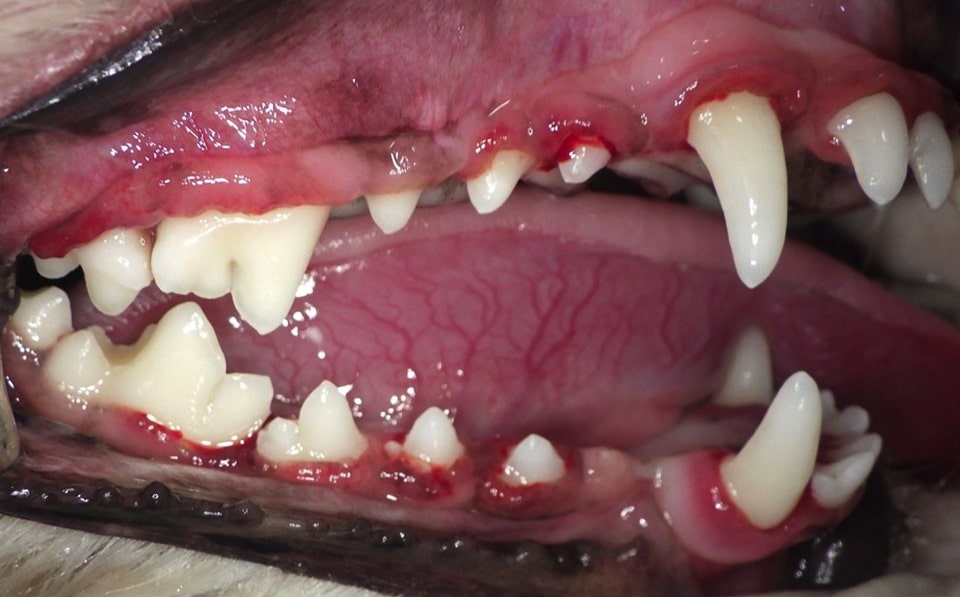

中度歯周病

処置前

処置後